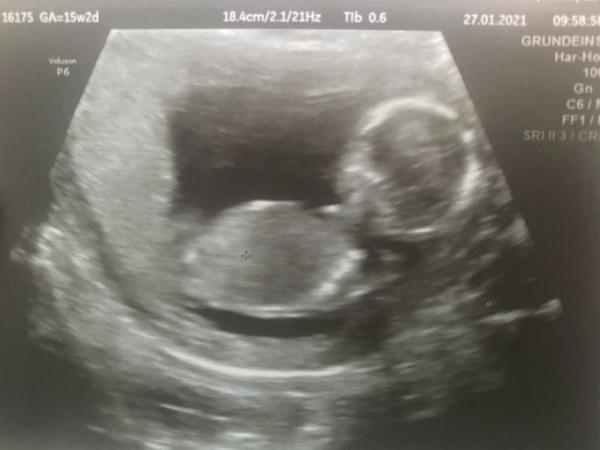

Hallo ihr Lieben, heute schwebe ich auf Wolke 7 und bin verliebt und verzückt! Der Termin beim Doc war super, wir hatten einen schönen langen Ultraschall und der Zwerg hat getobt. Es ist jetzt 15 cm groß und 130g schwer. Alles ist super entwickelt, wir haben den Magen, die Blase die Niere gesehen, die zwei Gehirnhälften und eine Pupille. Es hat den Mund geöffnet und uns angelacht. Fingerchen konnten wir auch zählen. Fuß ist schon 2 cm lang, beim letzten US war das ganze Baby 3,5 cm. Also alles prima! Sie konnte auch sehen was es wird, aber es steht auf einem Zettel in einem geheimnisvollen Umschlag und meine Nichte backt jetzt die Outingtorte! Ich bin grad einfach glücklich Liebe Grüße Neo PS: Bin bei 15 +2

Also ich bin nicht 100 % sicher, da der Ultraschall beim Messen 18,8 cm anzeigte. Dann sind die 15 cm die SSL. Die wird ja aber eigentlich nir bis zur 12. Woche gemessen. Es wiegt ja auch mit 130g deutlich mehr als 16 SSW mit 100g sagt.